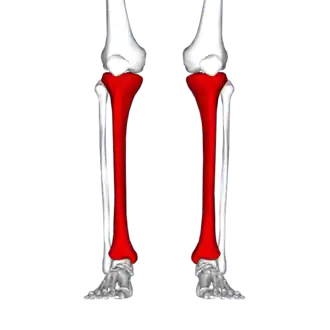

Attelle de tibia

Une attelle de tibia est une douleur le long du bord interne du tibia due à une inflammation des tissus dans cette région [2]. Généralement, elle s'entend entre le milieu de la jambe et la cheville[1]. Cette douleur est souvent sourde ou aiguë, et elle est couramment provoquée par l’exercice physique[2]. Elle disparaît généralement lors des périodes de repos[3]. Les complications peuvent inclure des fractures de stress[1].

Les attelles tibiales surviennent typiquement en raison d'une activité physique excessive[2]. Les groupes couramment touchés comprennent les coureurs, les danseurs et le personnel militaire [1]. Le mécanisme sous-jacent n’est pas tout à fait clair[1]. Le diagnostic est généralement basé sur les symptômes, avec une imagerie médicale réalisée pour exclure d'autres causes possibles [1].